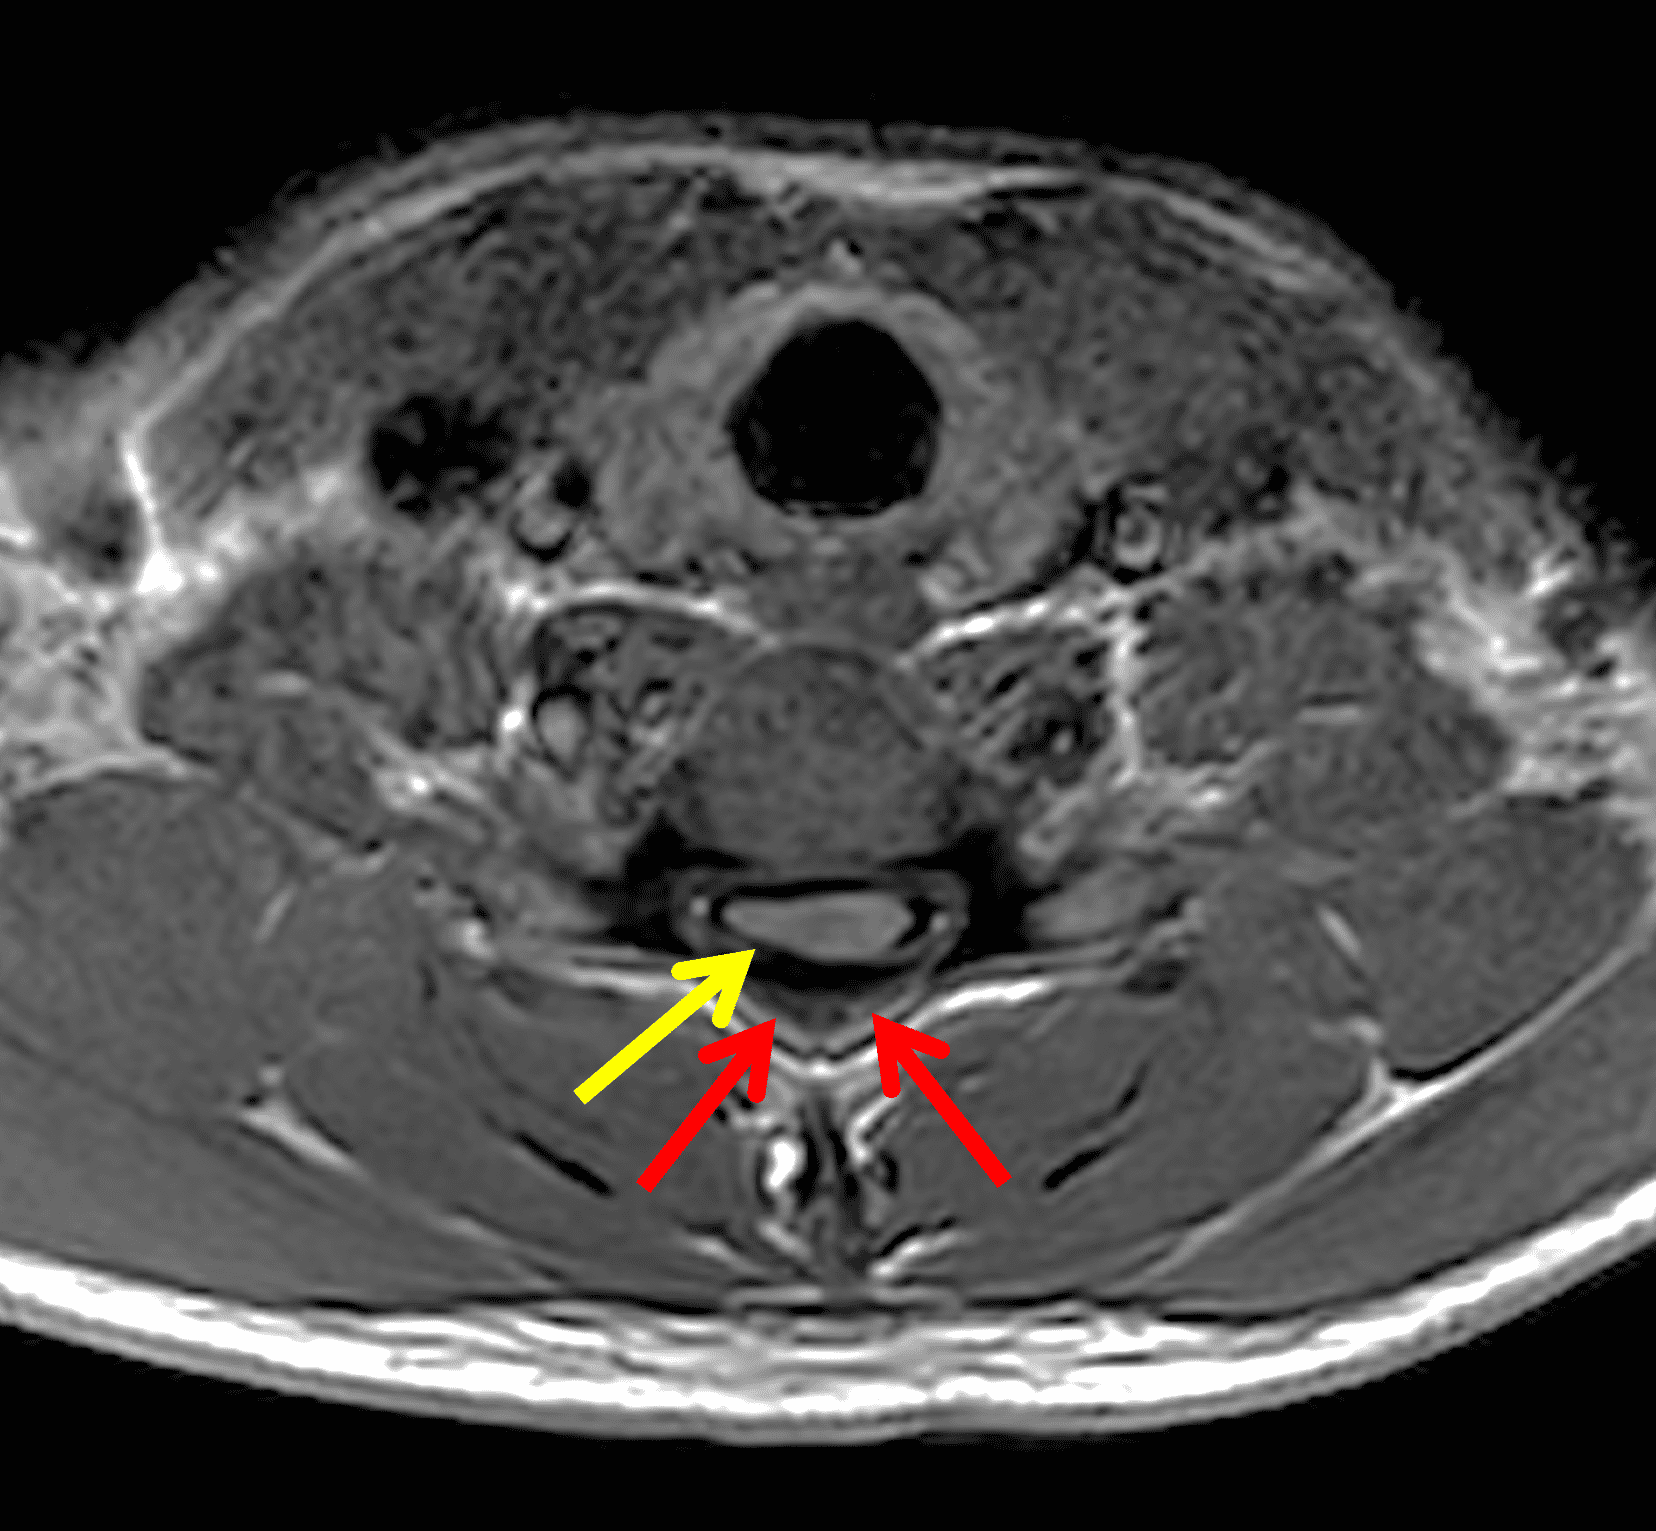

Figure 2: Neutral images of the cervical spine. Sagittal (2A) T2-weighted, (2B) T1-weighted, and (2C) STIR images show mild kyphosis, an enlarged posterior epidural space with loss of attachment of the dura (red arrows), and cord atrophy at the C6 level (yellow arrow). Subtle cord hyperintensity on the water sensitive images at the C7 level (green arrows) likely represents gliosis. (2D) Axial T2-weighted image shows enlargement of the posterior epidural space, right greater than left (red arrows). (2E) Axial T1-weighted image shows an enlarged posterior epidural space (red arrows) and cord atrophy, more severe on the right (yellow arrow).

The LOA sign was proposed as a finding suggesting HD on neutral position MRI of the cervical spine.29 The degree of loss of attachment of the posterior dural sac and subjacent lamina are evaluated on each side of the lamina at C4 to C6 levels on axial T2-weighted images, with separation along more than one-third of the lamina on one or both sides considered positive for LOA. To assess the degree of LOA, the lamina is defined medially by the point of junction of the lamina and laterally by a tangential line along the medial aspect of the pedicle and then divided into three equal parts (Figure 6). The LOA sign was found to have a sensitivity of 93.5% and specificity of 98% for HD. The LOA sign was investigated in the first multisite North American study by Lehman et al.5 and found to have a lower sensitivity of 70% but similar specificity of 100%. The authors confirmed that the LOA sign and other findings are often present on neutral position MRI and in the appropriate clinical scenario, should raise suspicion and prompt further assessment by flexion MRI to confirm the diagnosis.

Figure 6: Axial images demonstrating the loss of attachment (LOA) sign. (6A) T2-weighted and (6B) T1-weighted images in a normal spine (same patient as Figure 3). Yellow lines mark the lateral extent of the laminae, which have been divided into thirds (yellow dots). The posterior dura (red arrows) is firmly attached to the lamina. (6C) T2-weighted and (6D) T1-weighted images of a spine with HD (same patient as Figure 1) show the lamina divided into three equal parts (yellow lines and dots) and displacement of the posterior dural sac, right greater than left, with loss of attachment (red arrows). The separation involves more than one-third of the length of the lamina on both sides.